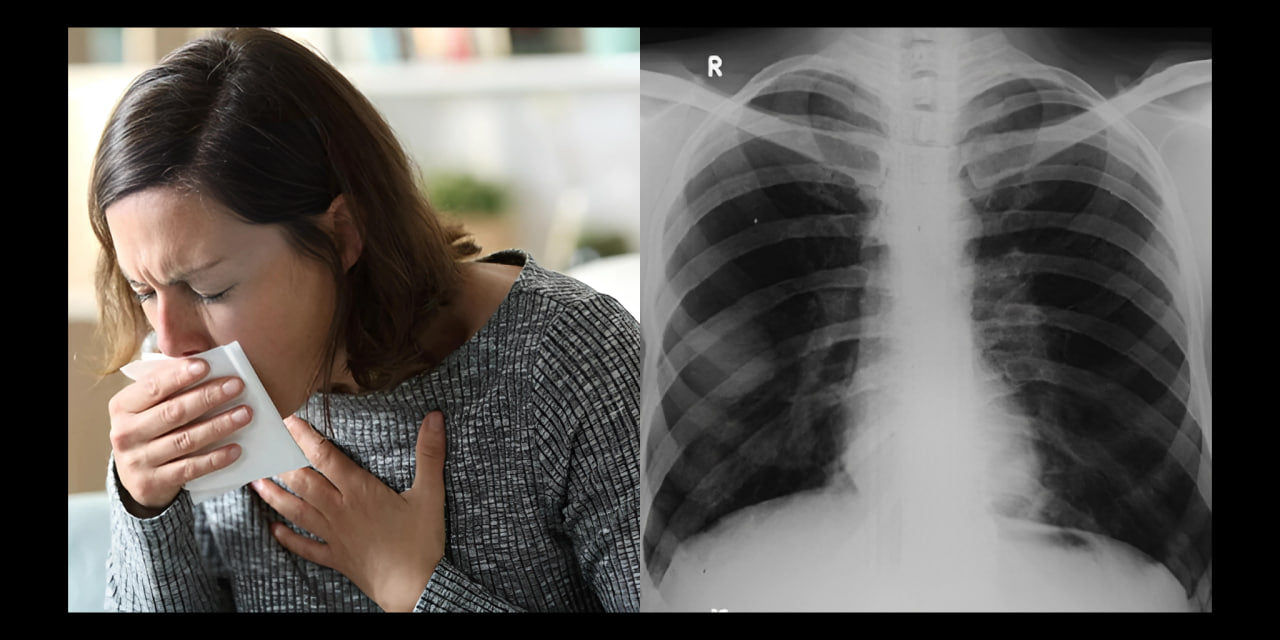

Har du ofta andnöd, hosta eller känner att dina lungor inte fungerar optimalt? Även om din läkare kanske försäkrar dig om att allt är bra, sitter du fortfarande kvar med symptomen. Upptäck min historia här och få reda på de positiva förändringar jag har gjort i mitt liv.

Mitt namn är Francesca van Vught, och under mer än fyra år led jag av hosta, andningsproblem och andnöd.

Under denna tid besökte jag flera läkare och genomgick nödvändiga tester. Jag hörde upprepade gånger att mina lungor såg bra ut och att jag inte hade något att oroa mig för.

När ingenting verkade hjälpa började jag göra min egen forskning. Jag insåg snabbt att lungorna är vitala organ i människokroppen och spelar en avgörande roll i andningssystemet.